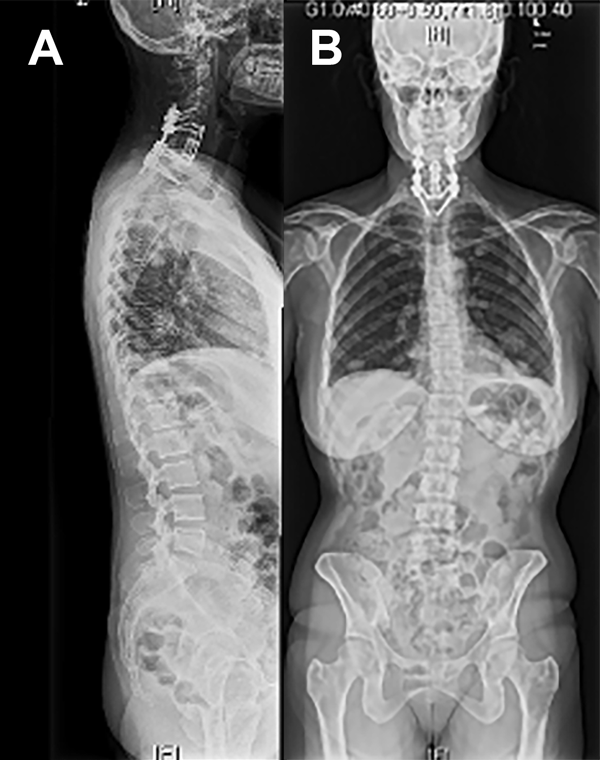

Figura 2. RX de columna complete AP y lateral que muestra corpectomía C6/C7. Estabilización anterior con cage, placa y tornillos. Fijación posterior desde C5-C6 a T1-T2 con barras y tornillos.

Se realiza cirugía en 2 tiempos; 1º: corpectomía de C6 y C7, estabilización anterior con cage, placa y tornillos; y 2ª: fijación posterior desde C5-T2 con barras y tornillo transpediculares.